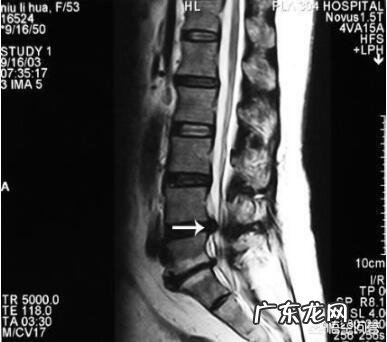

1.L4-5椎间盘突出症

文章插图

可半夜痛醒 , 疼痛部位在臀部外侧 , 腿外侧 , 咳嗽打喷嚏也会疼痛 , 早晨起床的时候腿痛多数是弯腰的时候出现 。